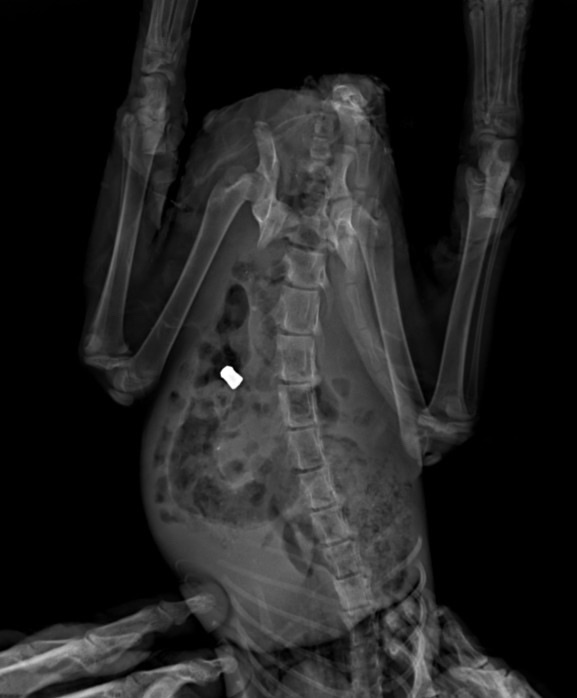

Перелом таза и ПУЛЯ в брюшке малюсенького котеночка!

Сколько к нам поступало животных с пулями, не представляете. Котёнок тоже поступил в один день с щенком и у обоих ПУЛЯ! У кого поднимается рука стрелять в малышей, даже представить страшно… Получится ли в этот раз помочь, не известно. Но, точно знаем, что если ничего не делать, это верная смерть БЕЗ ШАНСА, даже малейшего…

У малыша отсутствует чувствительность задних конечностей, некроз в паховой области. Естественно котёнок ходит в туалет по-большому и по-маленькому самопроизвольно. В связи с этим очень нужны пеленки 60*90 https://www.wildberries.ru/catalog/486716355/detail.aspx ! Так же у нас хватило денег только на рентгены 2 шт, капельницы ставим. Но, этого НЕ достаточно. Нужно сдать ПЦР (3 000 руб), так как если у котёнка вирусная инфекция, шансов практически не остается и само лечение необходимо другое.